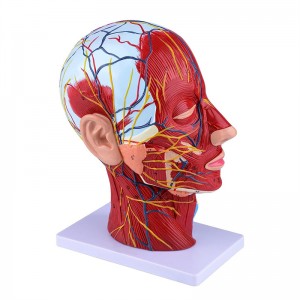

【1: 1 LifeSize】 Seksyen Median 1: 1 Model otot vaskular neural yang besar dan leher besar (sebelah kanan). Pengerjaan yang baik. Menawarkan pelbagai ciri anatomi.

【Model otot neurovaskular cetek】 Sangat terperinci, nombor yang ditandai, telinga boleh dilepaskan, memperdalam pemahaman otot, kapal, saraf dan struktur dalaman kepala & leher. Red-artery, biru-vein, kuning-saraf.

【Ciri -ciri】 Ia menunjukkan otot -otot cetek muka yang terdedah; saluran darah cetek & saraf muka & kulit kepala; struktur dalaman kelenjar parotid & saluran pernafasan atas; Struktur keratan rentas sagittal tulang belakang serviks.